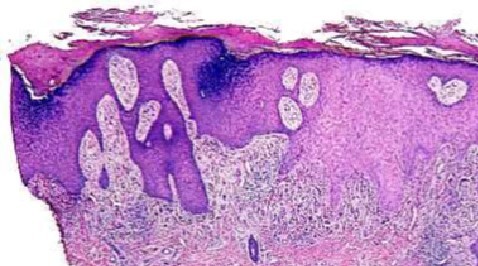

LICHEN PLANUS (LP)

LP DDx

Differential Diagnosis